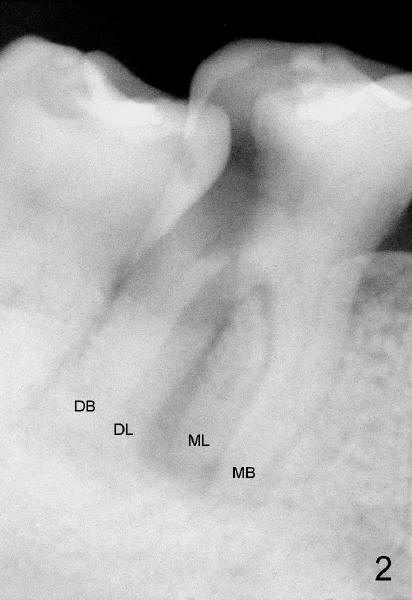

A healthy 43-year-old lady requests saving the tooth #30 with large DO caries and perioapical radiolucency (Fig.1). The tooth appears to have mesial (M) and distal (D) roots. Different angulation PA (Fig.2) and Bitewing (Fig.3) show that there are totally 4 roots/canals, which is not noted by the operator before RCT or after initiation of RCT (Fig.4). The distal canal orifice is not in the center. The distolingual (DL) canal orifice is searched without success. MB, ML, and D canals are debrided with rotary file 30/.04 at working lengths (WL).